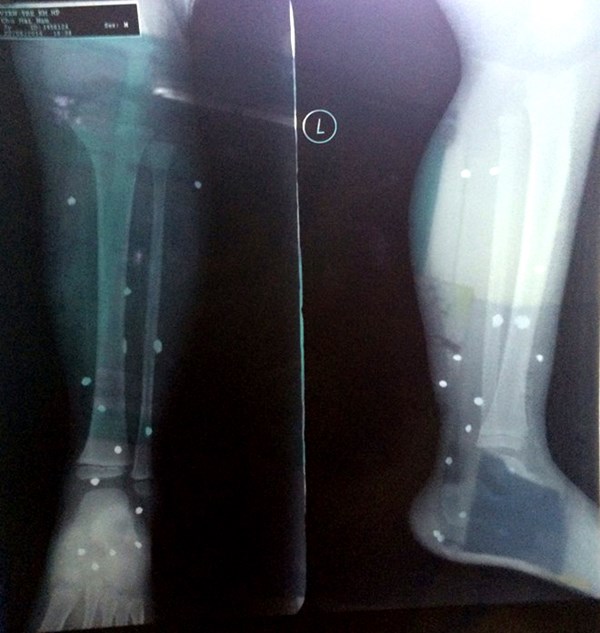

Do đứng ở gần cửa, Chu Hải Nam (4 tuổi, con trai anh Tấn) bị các mảnh đạn găm la liệt ở chân trái. Cháu bé khóc thét vì sợ hãi và đau đớn.

| Hình ảnh chụp X-quang các thương tích của bé Nam. |

16h cùng ngày, Nam được đưa đến cấp cứu tại bệnh viện Trẻ em Hải Phòng. Tại đây, các bác sĩ lấy từ chân bệnh nhân 15 viên đạn (kích thước khoảng 0,5 cm)

Từng cấp cứu nhiều trường hợp bị súng hoa cải bắn, các bác sỹ nơi đây xác định, bé trai bị thương do súng bắn đạn đạn hoa cải.